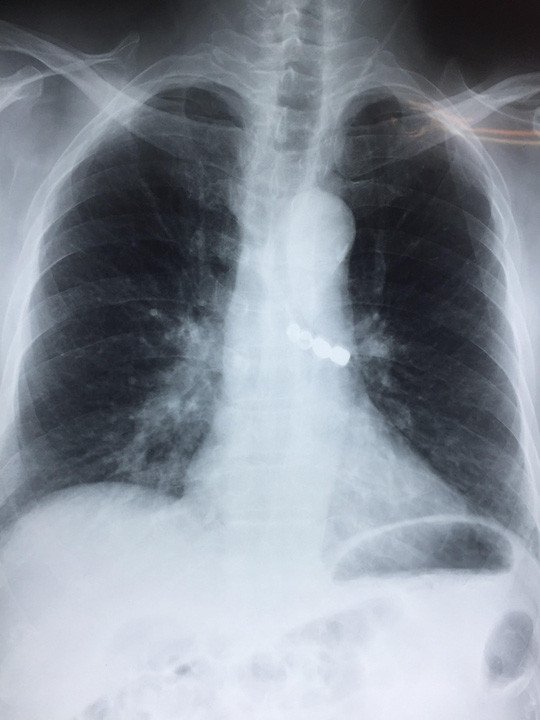

Dị vật nằm sâu trong phế quản khiến bệnh nhân khó thở, đe doạ tính mạng - Ảnh: Bác sĩ cung cấp |